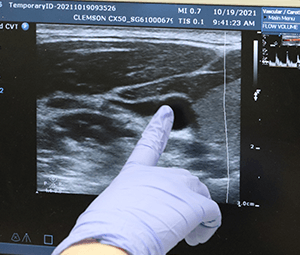

When you graduate, you’ll be ready for an entry-level position in a cardiovascular diagnostic department. As a licensed cardiovascular technologist, you’ll be an extension of the cardiologist: You’ll use cutting-edge machinery to produce images of the heart and blood vessels that guide diagnoses and treatments of cardiovascular diseases. You might review a patient’s history, perform cardiovascular diagnostic and therapeutic procedures or analyze patient data for interpretation by a physician.